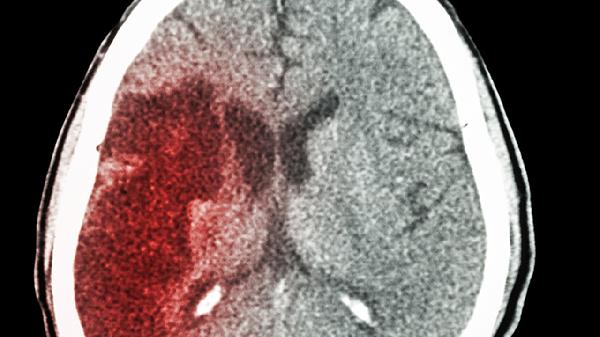

45岁大叔深夜脑梗离世!提醒:4种食物容易堵塞血管,少吃为妙

深夜的急诊室又传来令人心碎的消息——45岁的王先生因突发脑梗抢.救无效。翻开他的饮食记录,医生发现那些"血管杀手"几乎天天出现在餐桌上。血管就像家里的下水道,有些食物吃多了,真的会像油脂堵塞管道一样让血管"堵车"!

那位离世的王先生,体检报告上"低密度脂蛋白偏高"的提示已经出现了三年。血管的堵塞从来不是突然发生的,而是日积月累的"慢性谋杀"。从今天开始,检查一下你家厨房,把这些"血管杀手"请出购物清单吧!记住,最好的治疗永远是预防,别让明天的急诊室又多一个本可避免的悲剧。